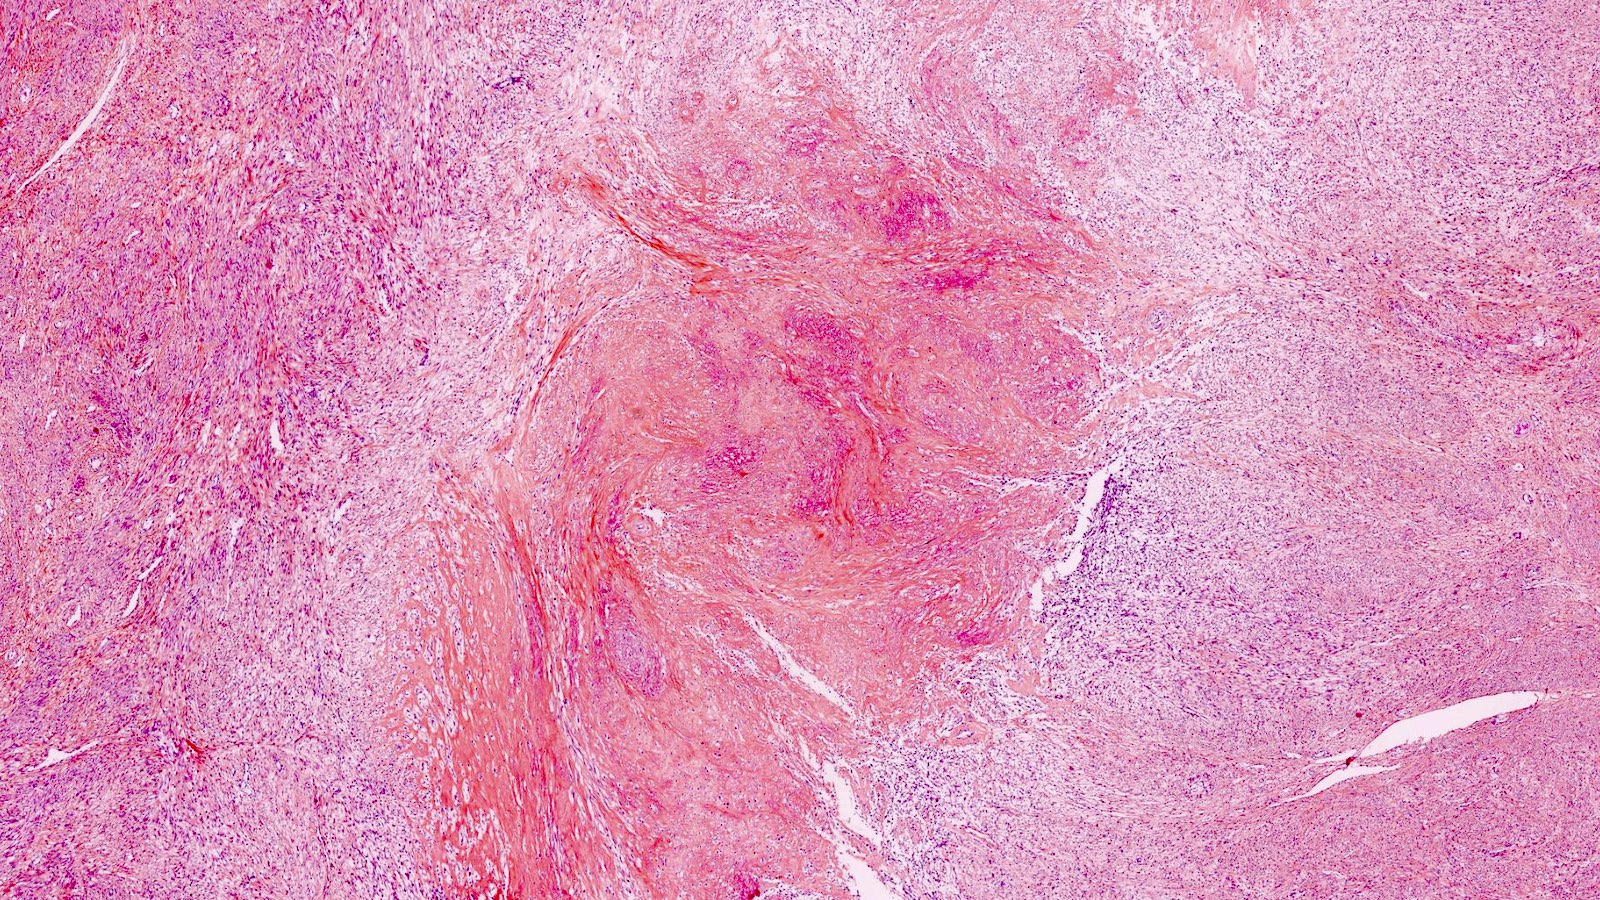

Gross description

- Location in the uterus: intramural, submucosal and subserosal

- Often multiple

- Typically well circumscribed but nonencapsulated

- On cut surface: white or tan-white, whorled, firm, bulging

- Hemorrhage and infarction can be present in large tumors

- Calcifications can be present

- Reference: Mod Pathol 2016;29:S104

Gross images